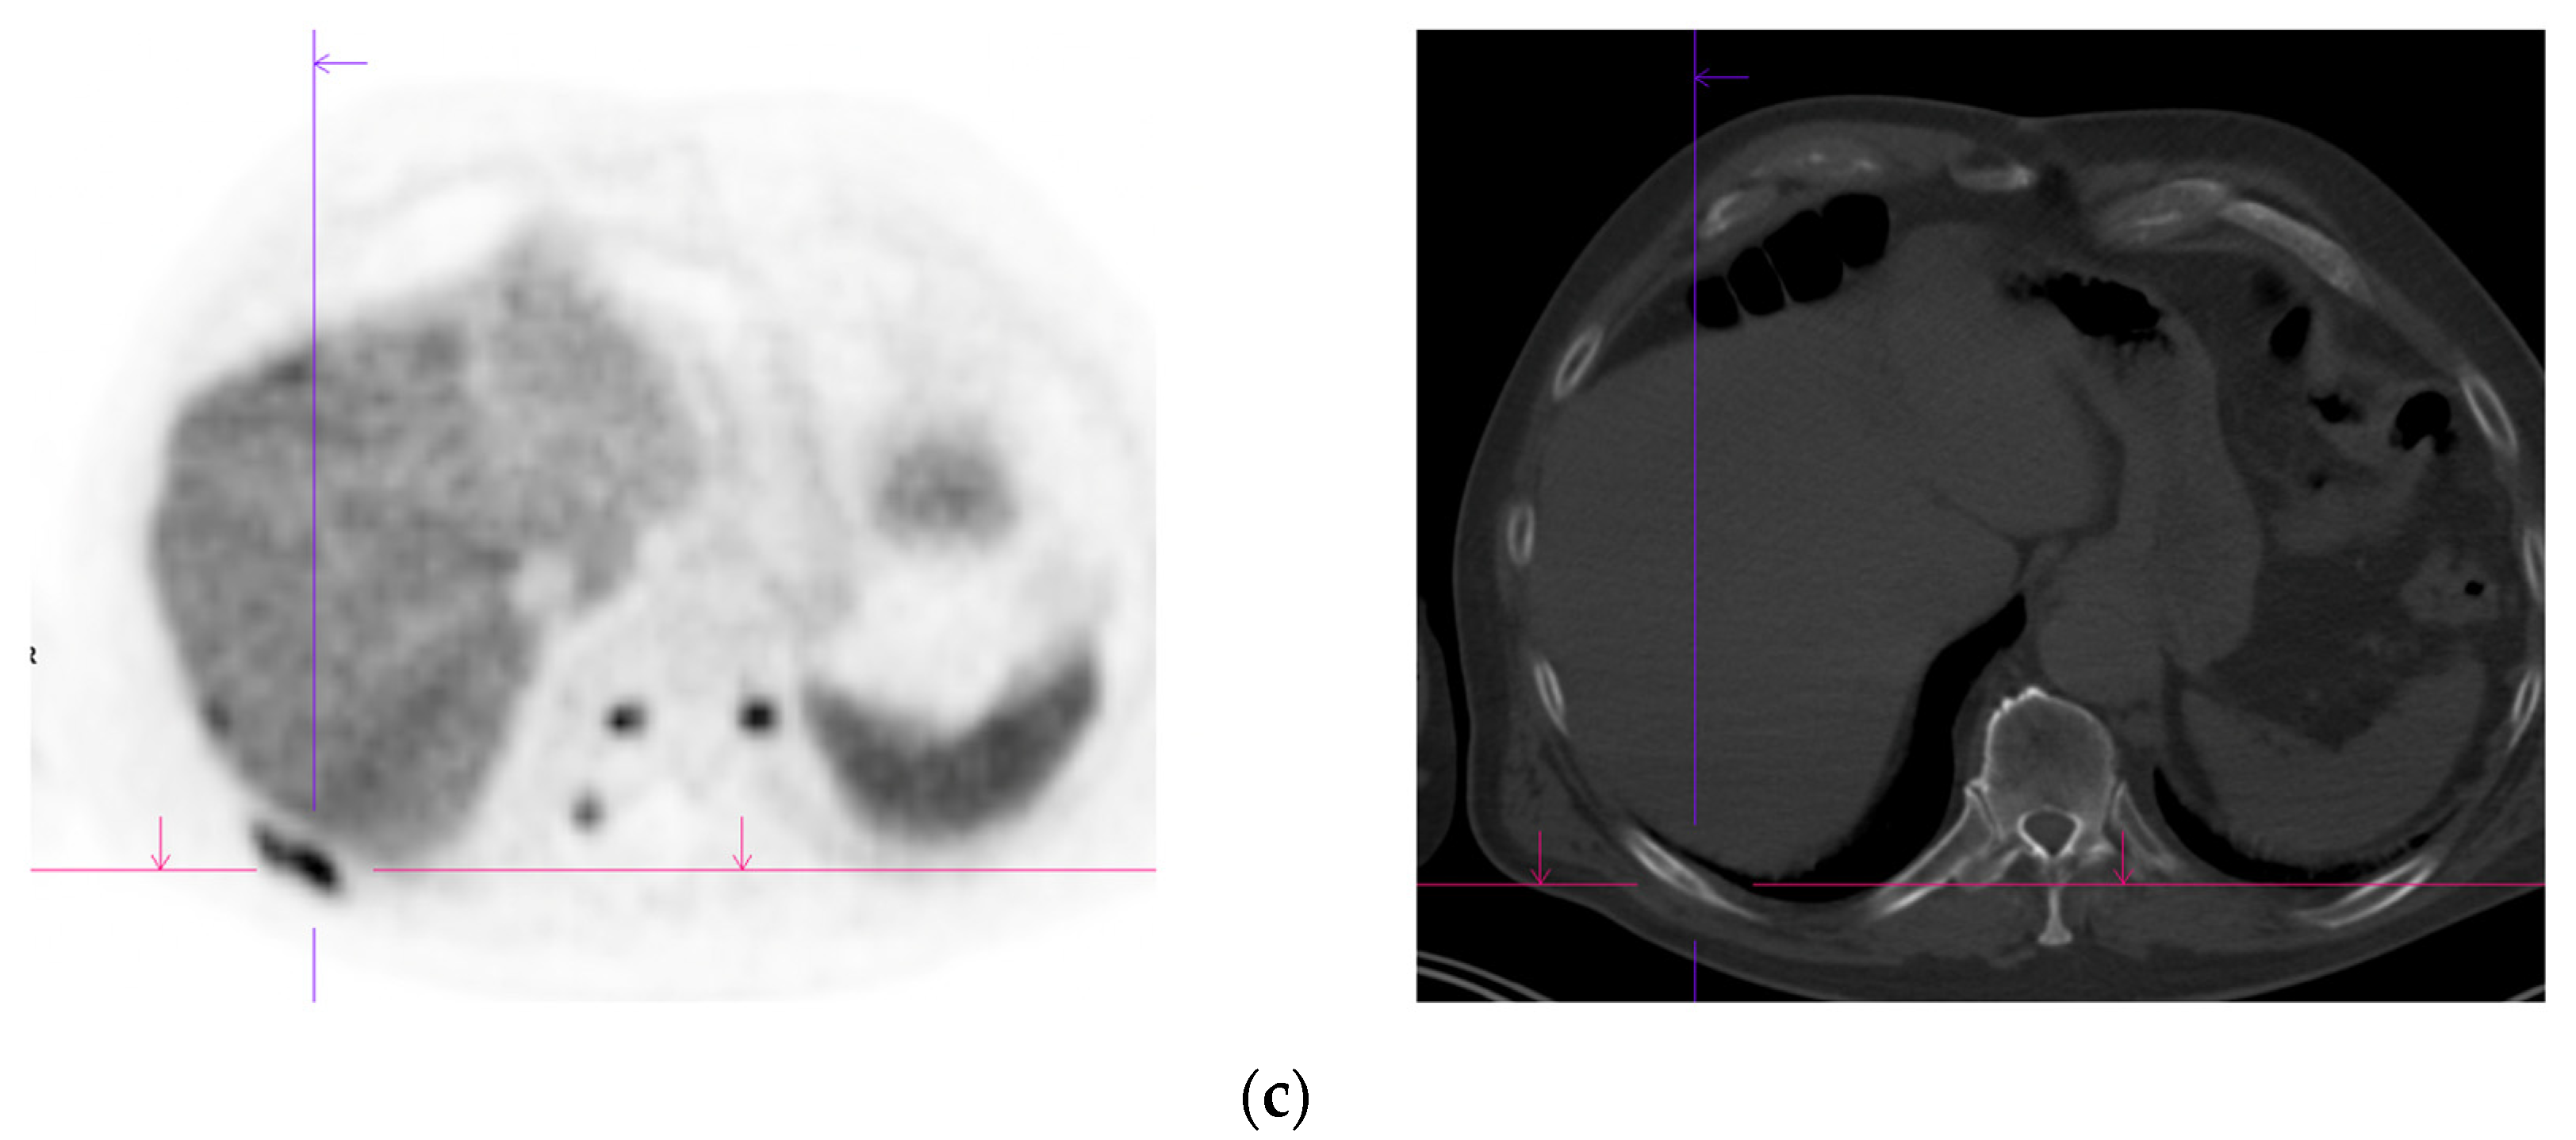

- Damjanovic, J.; Janssen, J.C.; Prasad, V.; Diederichs, G.; Walter, T.; Brenner, W.; Makowski, M.R. 68Ga-PSMA-PET/CT for the evaluation of liver metastases in patients with prostate cancer. Cancer Imaging 2019, 19, 37. [Google Scholar] [CrossRef]

- Damjanovic, J.; Janssen, J.C.; Furth, C.; Diederichs, G.; Walter, T.; Amthauer, H.; Makowski, M.R. 68Ga-PSMA-PET/CT for the evaluation of pulmonary metastases and opacities in patients with prostate cancer. Cancer Imaging 2018, 18, 20. [Google Scholar] [CrossRef]

- Pyka, T.; Weirich, G.; Einspieler, I.; Maurer, T.; Theisen, J.; Hatzichristodoulou, G.; Schwamborn, K.; Schwaiger, M.; Eiber, M. 68Ga-PSMA-HBED-CC PET for Differential Diagnosis of Suggestive Lung Lesions in Patients with Prostate Cancer. J. Nucl. Med. 2016, 57, 367–371. [Google Scholar] [CrossRef]